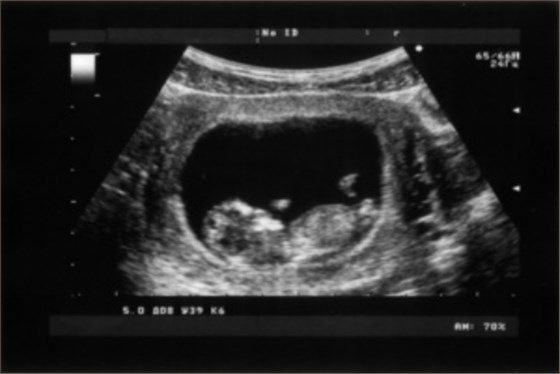

胎兒超聲檢查心臟,通常在孕中期進行。胎兒心臟發(fā)育在不同孕周有不同的變化,一般在孕22-28周進行胎兒心臟超聲檢查,可在胎兒頭部、心臟、四肢等部位,發(fā)現(xiàn)明顯的異常情況,應及時進行相應的處理。

2、心臟:正常心臟應在孕第6周開始發(fā)育,此時心臟已出現(xiàn)結構性改變,可以分辨出頭部、體部、左右心房及右心室,同時可觀察到室間隔及二尖瓣、三尖瓣是否存在結構性異常;

4、其他情況:心臟發(fā)育在孕22-28周時較為明顯,此時胎兒大小通常為長45cm左右,體重為5-6g。此時胎兒的心臟大小約為100-200mm,胎兒形態(tài)以圓形或橢圓形為主,心尖位于第5肋間隙內(nèi),基本上與胸部對稱,主動脈短而厚,呈直角左邊緣狀態(tài)。

胎兒超聲檢查時可清楚地顯示出胎兒各個器官及組織的發(fā)育情況,對于胎兒畸形、心臟發(fā)育異常等情況的診斷有重要價值。因此,建議孕婦定期遵醫(yī)囑進行超聲檢查,以明確胎兒的生長發(fā)育情況。